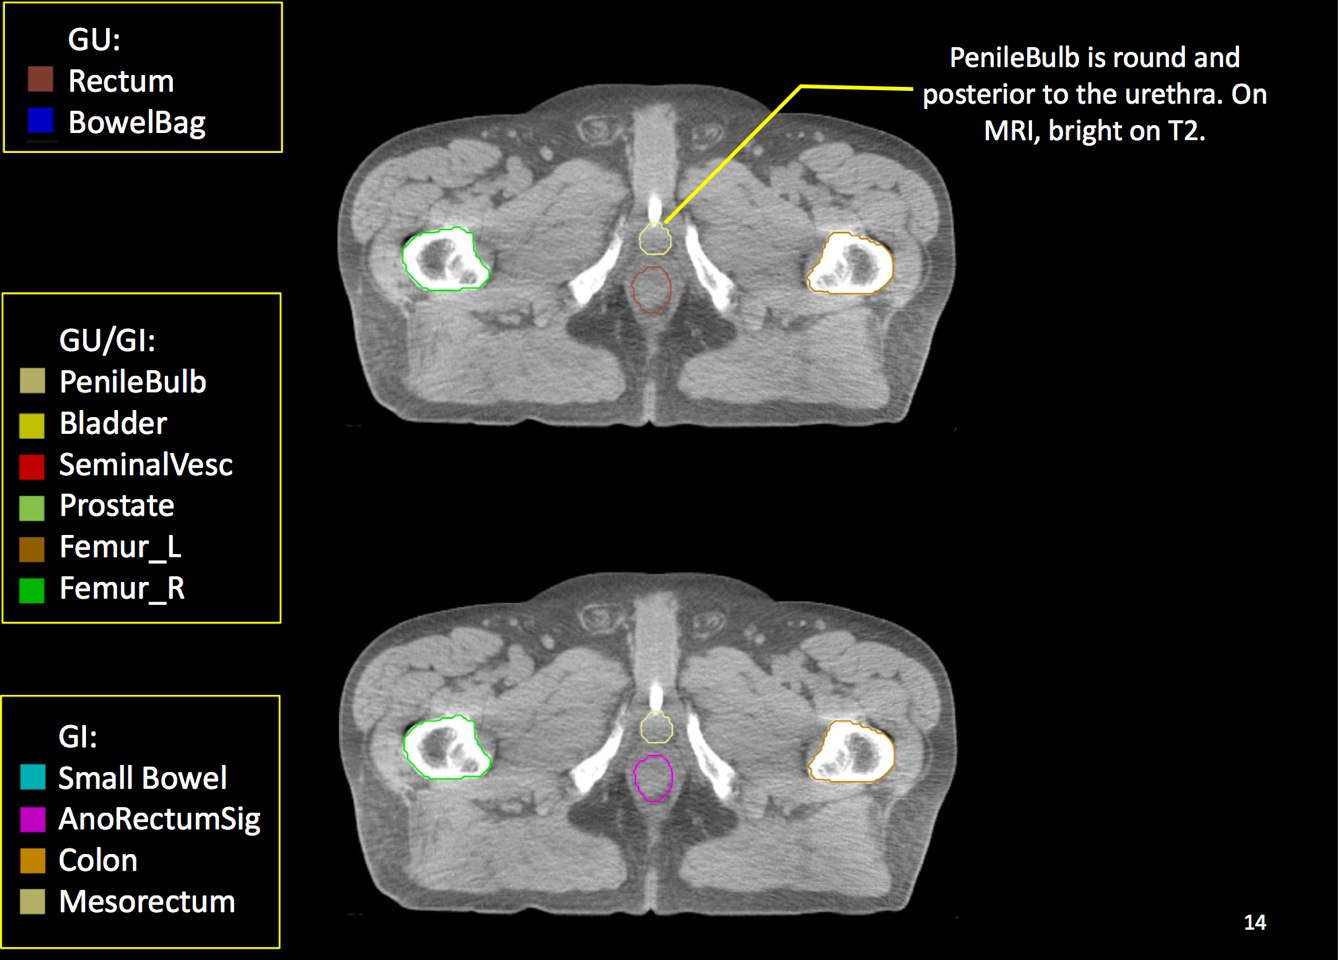

At a minimum, the following contours should be available to the planners:

• prostate

• seminal vesicles (treat at least proximal if risk calculated > 15% --ucsf)

• pelvic lymphatics (if treatment indicated -- risk > 15% -- ucsf)

• femoral heads

• rectum

• bladder

• bowel (where necessary due to bowel prolapsing below the bladder)

• penile bulb

The target volume (CTV) is defined as the prostate and seminal vesicles. The planning target volume expands the CTV to take into account setup uncertainties, both systematic and physiologic. By using daily image guidance, where available, physiologic parameters are more controlled and allow the reduction of CTV expansion required to fully cover the prostate and adjacent tissue at risk.

There is significant variation of contours and techniques. The apex and base are regions most susceptable to variation. 3D perspectives help signficantly reduce this variation using transverse, sagital and coronal projections to determine the true extent of the prostate. More recently contouring atlases have been developed by the RTOG with grant assistance from the NCI and are available here. The following images are obtained from the RTOG contour atlases as an excerpt demonstrating areas of potential uncertainty.

Penile BulbMean dose ≤ 52.5 Gy

There are recent efforts to standardize segmentation names for radiotherapy treatment planning. This is encouraged to allow for inter-institution comparisons, particularly on protocol patients, but it may also assist institutions in comparing dosimetry should additional radiotherapy or other dose questions arise. The normal clinical structures to be identified are: